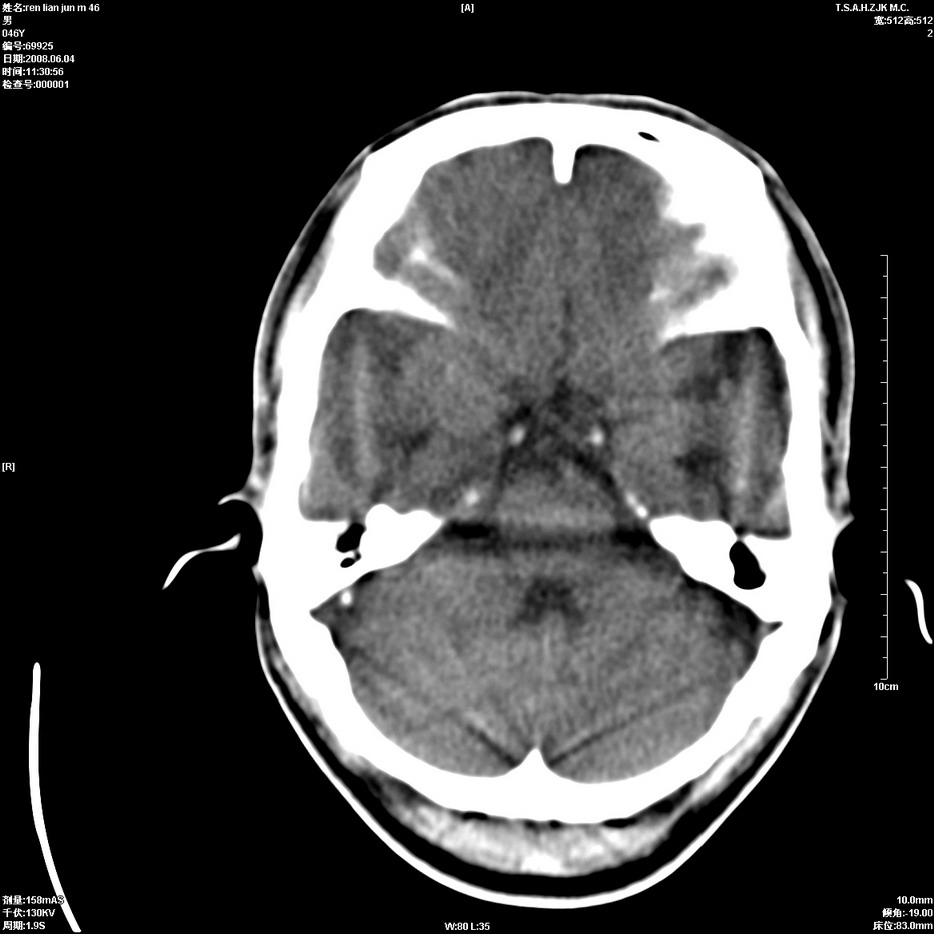

以下是引用qiu999在2008-6-5 17:14:00的发言:[br]考虑右肺中心型肺癌.颅内应做增强检查.

以下是引用形影不离在2008-6-5 19:18:00的发言:[br]右肺中心型肺癌并纵隔及左侧腋窝淋巴结转移,颅内应做增强检查。

以下是引用杀毒软件在2008-6-5 18:33:00的发言:[br]支持考虑右肺中心型肺癌,颅内病变是不是转移,不好说